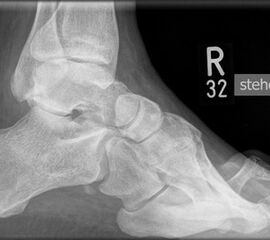

• Fuß belastet dp und seitlich (Abb. 14 und 15)

• Saltzman view (Abb. 16)

Zum Lesen der Bildbeschreibung und zur Vollansicht bitte die Bilder anklicken. Bilder: A. Simon

Typische Merkmale der Standard-Seitaufnahme des Fußes im Stand

• Knöchelgabel ist außen rotiert

• Talus und Calcaneus verlaufen fast parallel

• Sinus tarsi ist einsehbar

• Subtalare Gelenklinie verläuft horizontal und ist breit einsehbar

• Der Abstand Malleolus medialis zum Os naviculare ist verkürzt

• Der Calcaneus erscheint verkürzt

• Der Krümmungsscheitel des Fußes ist erhöht

• Calcaneus pitch ist meist erhöht, der Rückfuß Equinus ist eher selten 12